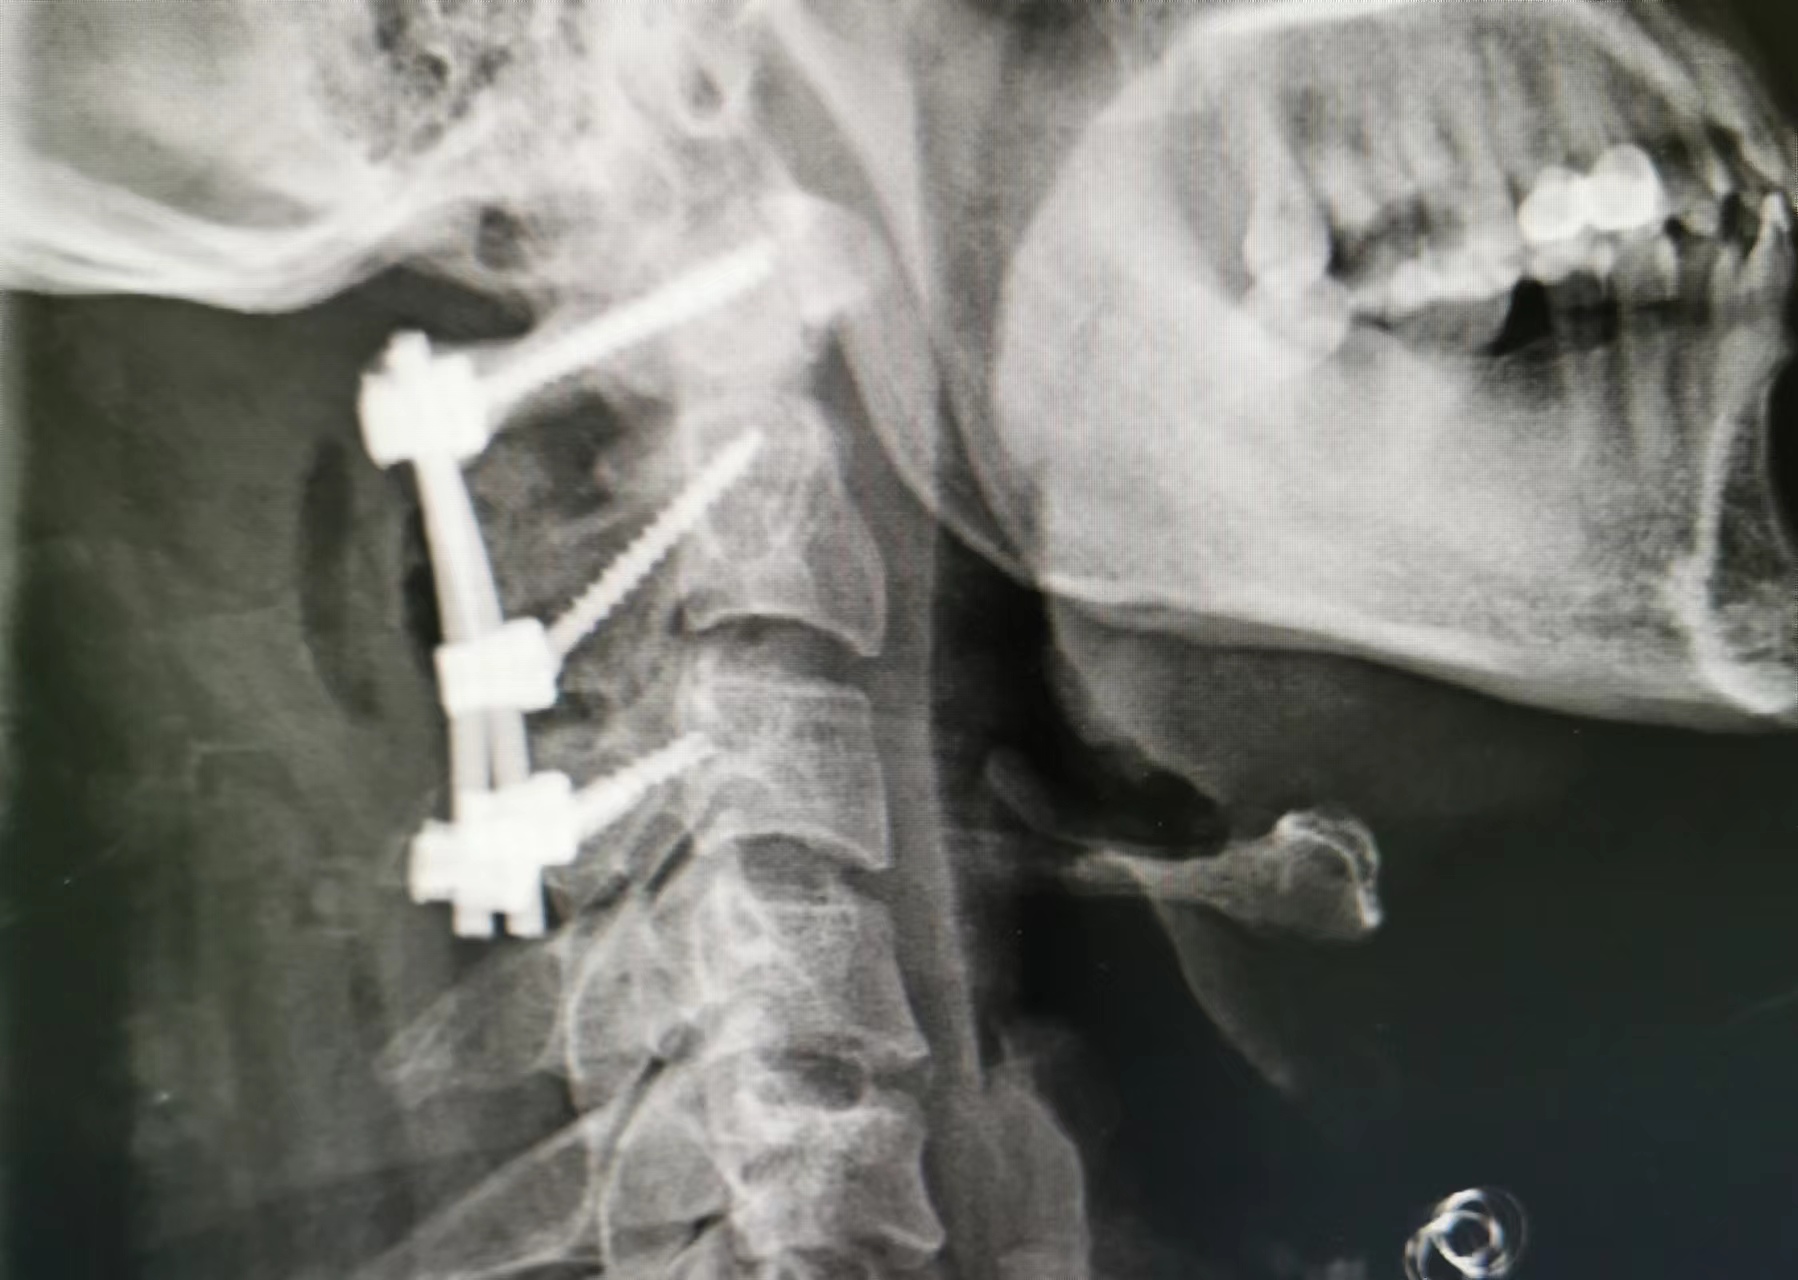

寰樞椎的內(nèi)固定治療、脊柱脊髓病損的手術(shù)治療

打破了脊柱手術(shù)生命禁區(qū)的限制,手術(shù)數(shù)量及質(zhì)量全市第一,處于省內(nèi)領(lǐng)先水平。